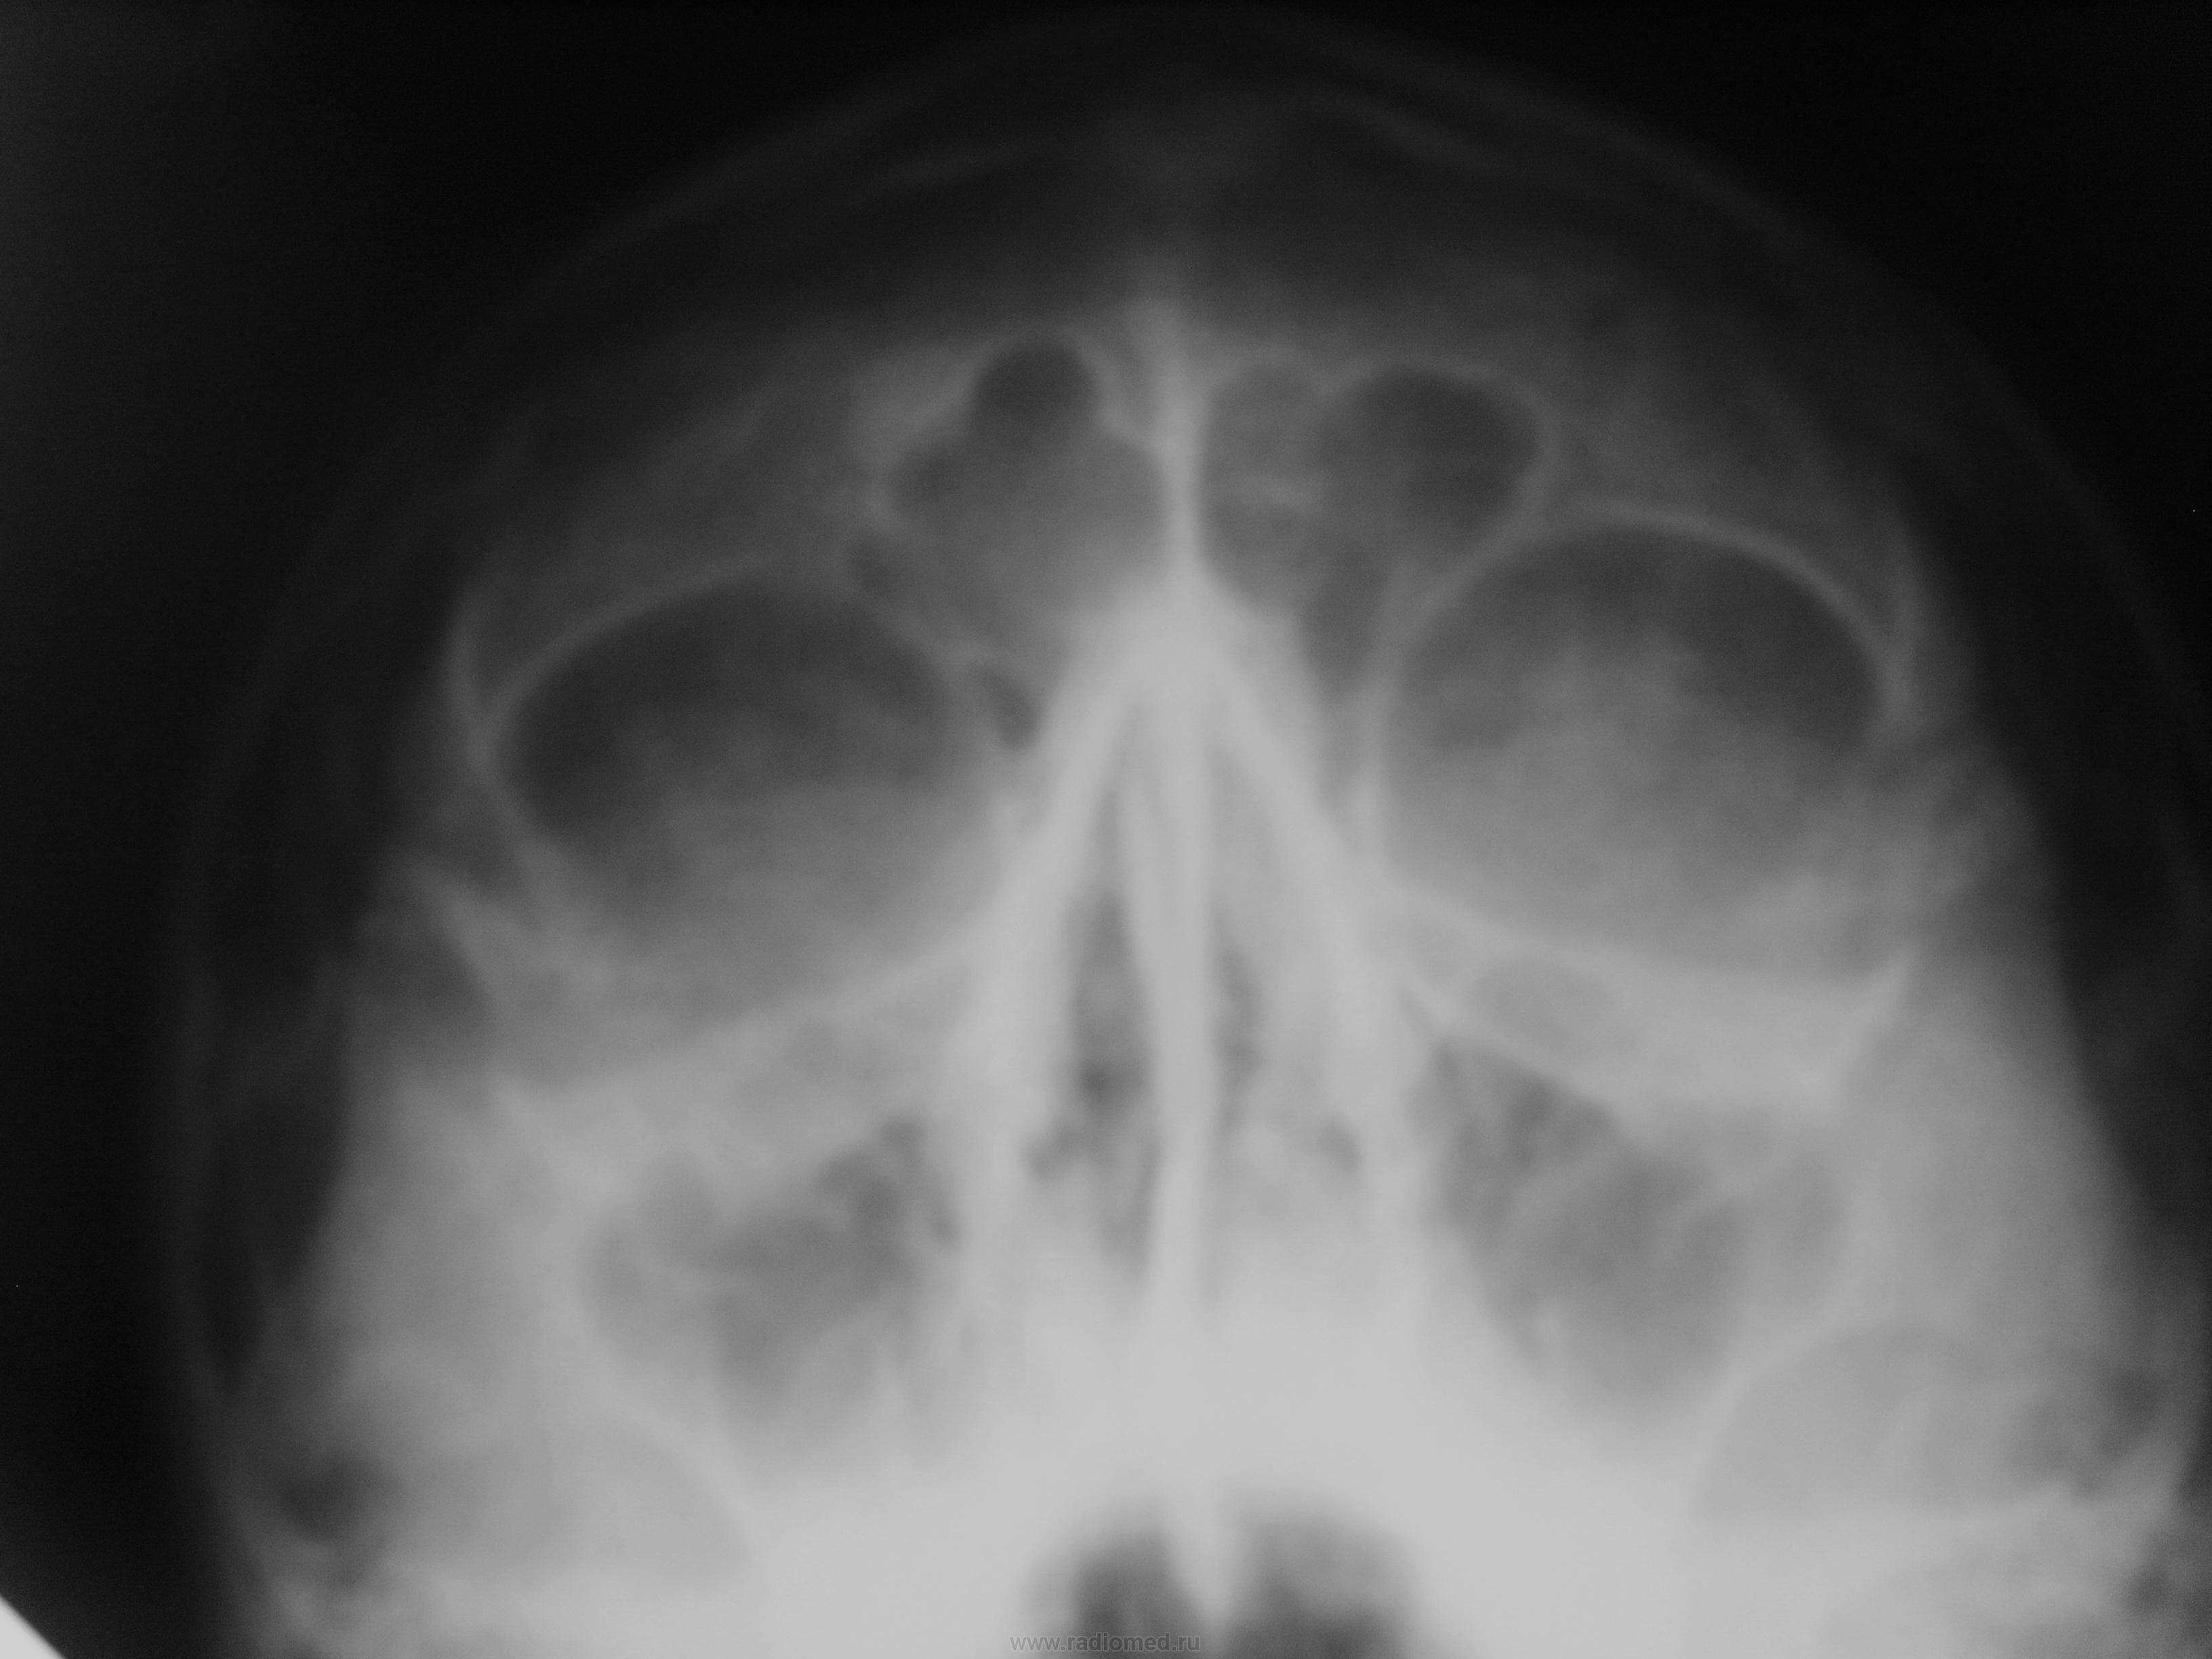

Выраженое утолщение слизистой оболочки правой гайморовой пазухи.

Выраженное утолщение слизистой правой гайморовой пазухи с наличием фиброзных тяжей. Снижение пневмотизации правой лобной пазухи и решетчатых клеток.

З-е: Хр. правосторонний гайморит. Правосторонний фронтит.

пристеночное понижение пневматизации верхнечелюстных пазух, больше - правой, ячеек решетчатой кости и фронтальной пазухи за счет отека слизистой оболочки.]